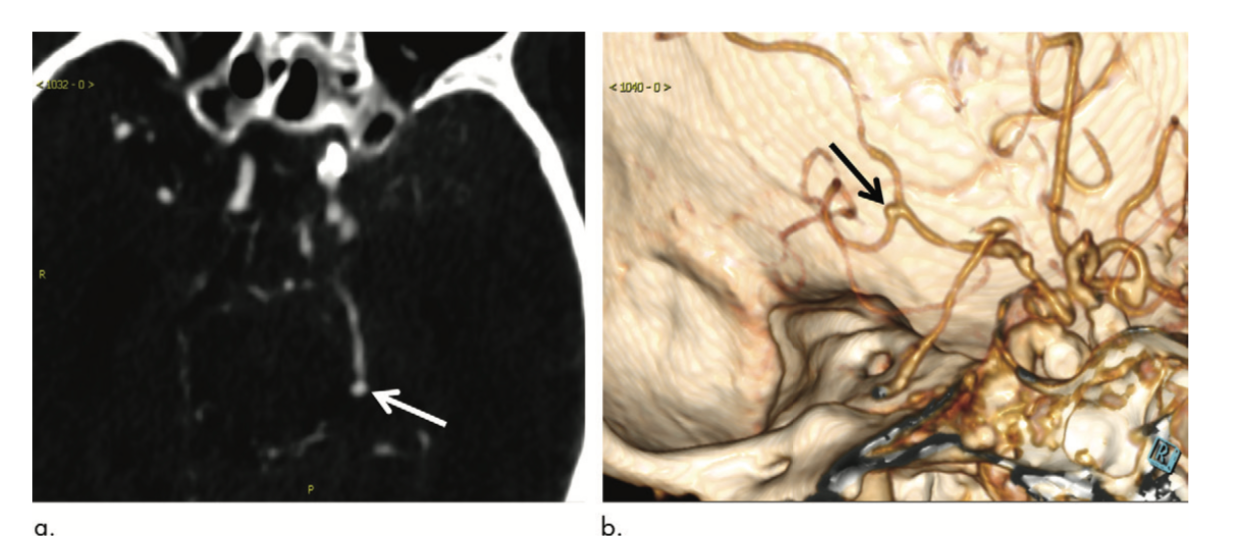

As Alzheimer’s disease progresses, more brain regions exhibit evidence of this link.

Modifying an existing imaging probe and labeling it with fluorine-18 improves providers’ ability to pinpoint protein accumulation – and differentiate between neurodegenerative conditions.